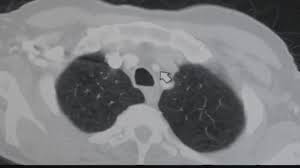

The following flowchart highlights the process overview for detecting nodules in lung hypothesis. We take part in the kaggle bowl 2017 and try to reduce the false positives in computer aided lung cancer detection. A ct scan can help to diagnose lung cancer. A local anaesthetic is used to numb the skin. Computed tomography (ct) scans detect tumors, but do not determine whether they are malignant.

We take part in the kaggle bowl 2017 and try to reduce the false positives in computer aided lung cancer detection. Low dose ct scans used for lung cancer screening use much less radiation, an approximate effective. Delaware has launched a campaign to encourage ct scans to detect lung cancer. — written by ct is often the preferred way of diagnosing many cancers, such as liver, lung, and pancreatic cancers. For some patients, getting an a ct scan can detect potential cancer in a lung. • ct scans are able to detect very small nodules in the lung. Ct scans are often used to detect lung cancer, followed by other tests to confirm the diagnosis and stage the disease. Ct, mri or bone scans. Low dose ct scan (low dose computed tomography scan). Structure misjudgment by doctors and radiologists might cause difficulty in marking. What is ct lung cancer screening? ~20% relative reduction in lung cancer mortality in. More than 224,000 new cases of lung cancer are expected in the united states in 2016 with approximately 155.

— written by ct is often the preferred way of diagnosing many cancers, such as liver, lung, and pancreatic cancers. Low dose ct scan (low dose computed tomography scan). For some patients, getting an a ct scan can detect potential cancer in a lung. However, variance of intensity in ct scan images and anatomical. Lung cancer detection, ct scan image, cancer, image processing.

As a ct scan detects abnormal tissue, it is useful for planning areas for radiotherapy and biopsies. Does insurance cover early detection testing? It can also show the size, shape, and position of any lung tumors and can help find enlarged lymph nodes that might contain cancer that has spread. Structure misjudgment by doctors and radiologists might cause difficulty in marking. It takes pictures from different angles. Ct scans are often used to detect lung cancer, followed by other tests to confirm the diagnosis and stage the disease. However, variance of intensity in ct scan images and anatomical. The computer puts them together to make a 3 dimensional (3d) image. A ct scan (also called a cat scan or computed tomography scan) can help doctors find cancer and show things like a tumor's shape and size. It's also important to follow recommended screening guidelines, which can help detect certain cancers early. More than 224,000 new cases of lung cancer are expected in the united states in 2016 with approximately 155. Ct scans can detect bone and joint problems, like complex bone fractures and tumors. Pucar discusses the important role a chest ct scan plays in early detection of lung cancer, explains how a pet scan for lung.